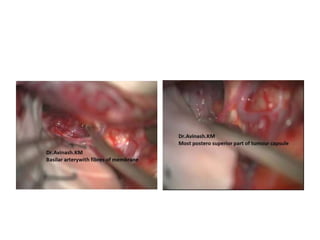

Craniopharyngioma removal -

Lilliquest membrane & Basillar artery

The basilar artery(BA) can be seen very tortuous.